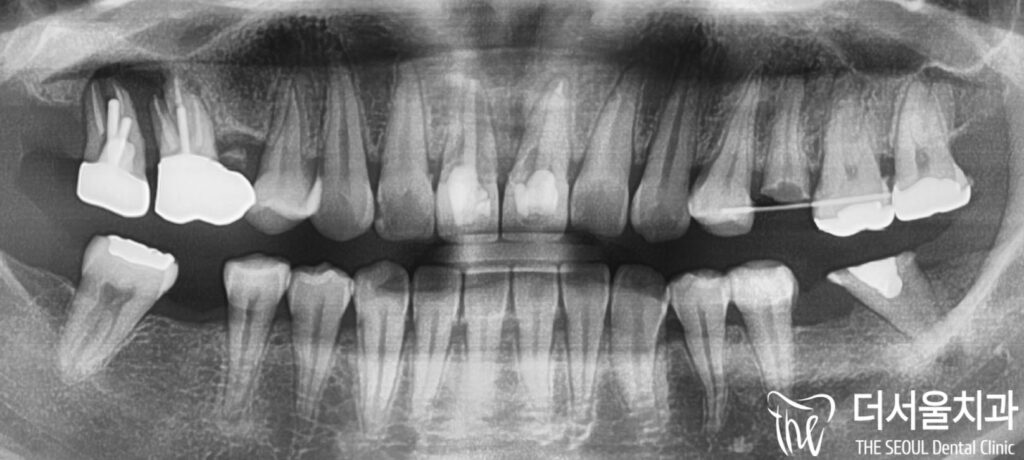

먼저 정확한 진단을 위해

엑스레이를 촬영해 보았습니다.

4년 전 진료 기록

저희가 해드린 보철은

이전 진료 기록과 비교하여

보니 별다른 문제 없이

잘 사용하고 계신 것을 확인했습니다.